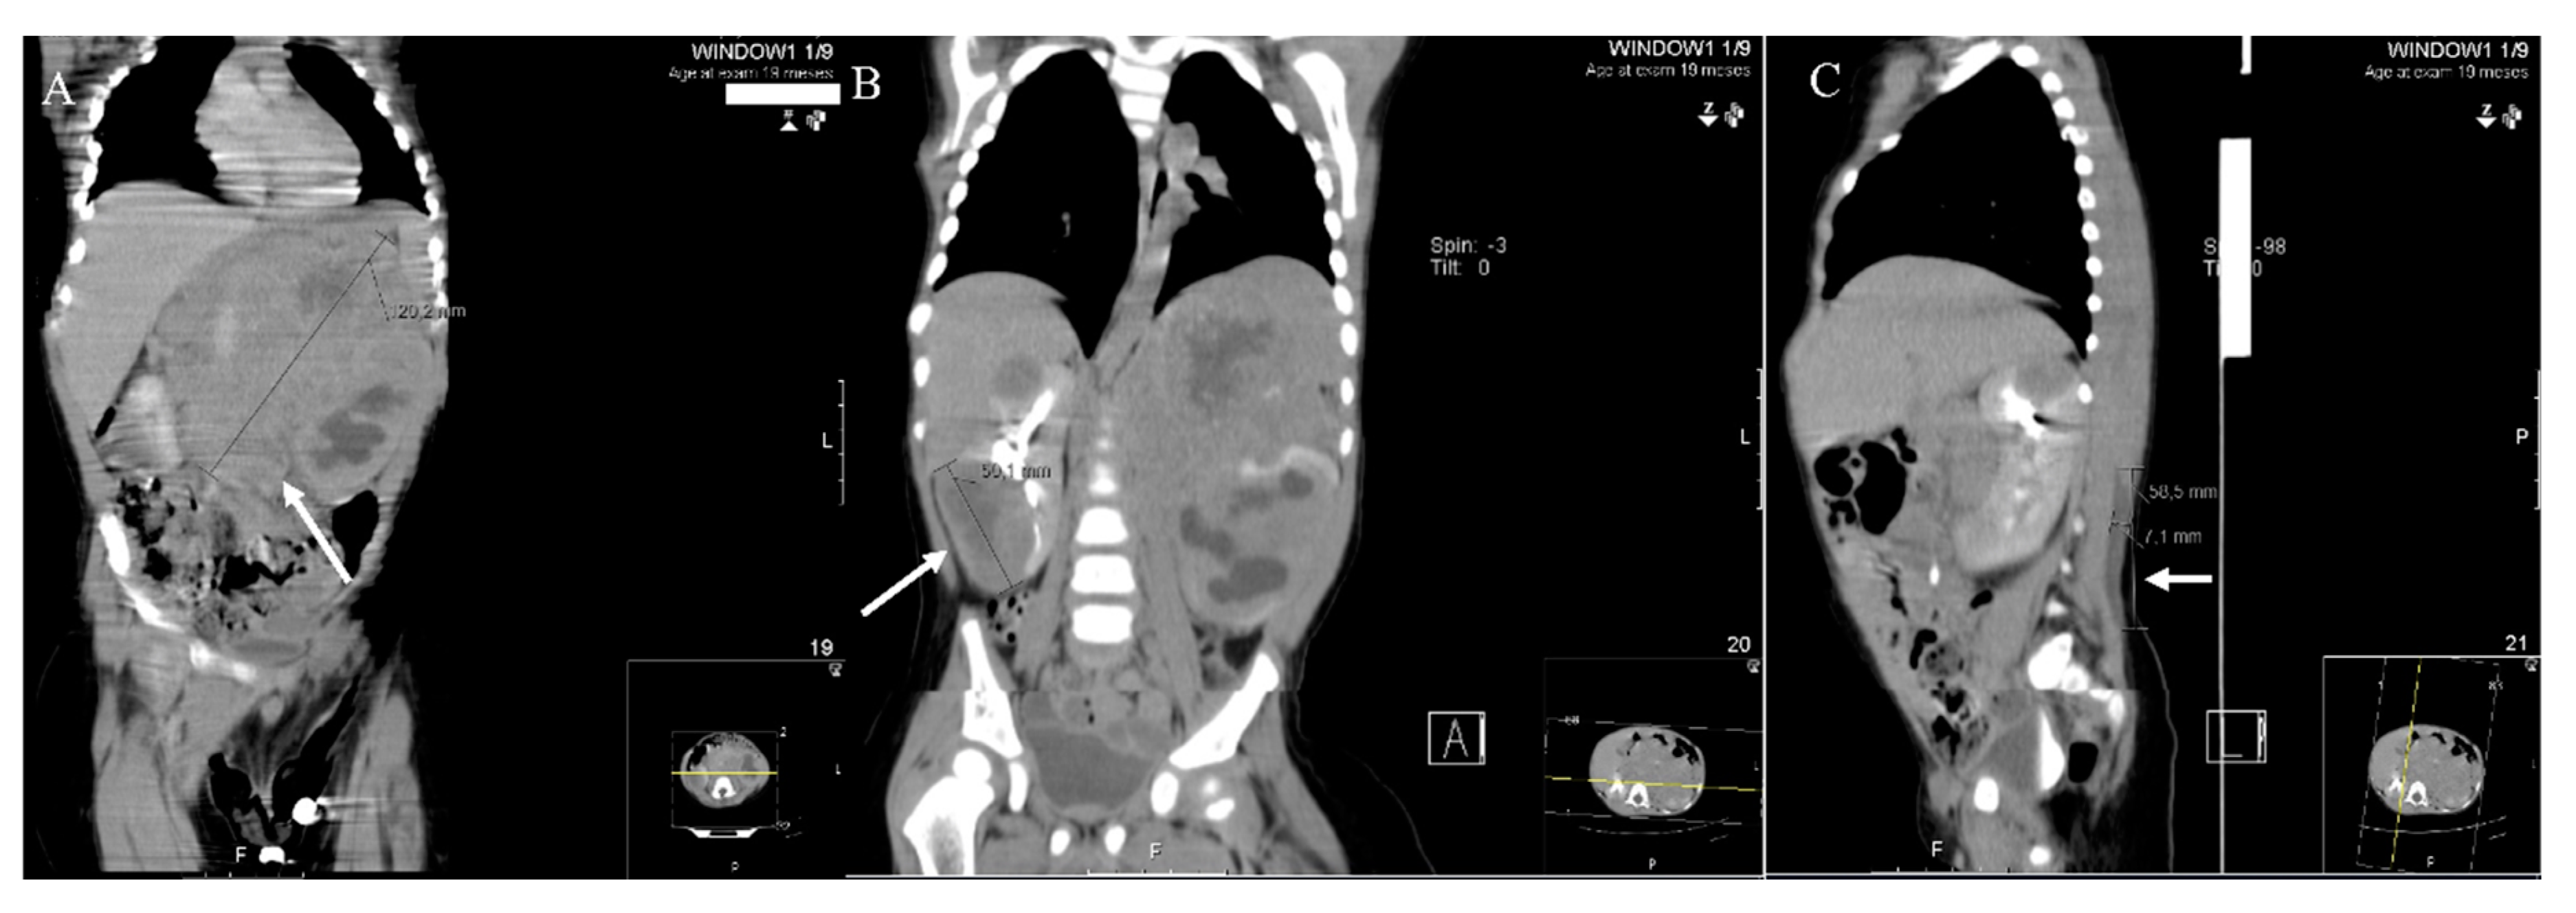

2. Results